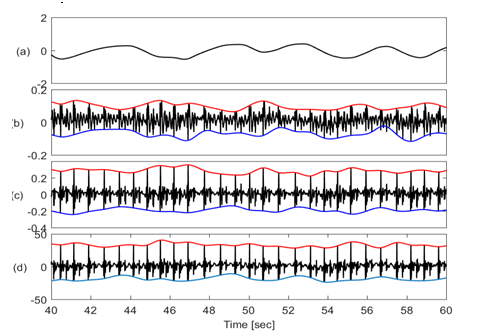

Figure 2 shows the physiological signals with their upper and lower envelopes suggesting that baseline and amplitudes of these signals noticeably vary with respiration.

Figure 2 Traces of different physiological signals (a) Lung volume (b) SCG-craniocaudal with upper & lower envelope (c) SCG-lateral with upper & lower envelope (d) SCG-dorsoventral with upper & lower envelope. SCG envelopes suggest that the baseline wondering, and amplitude modulation of these signals have a period similar to respiration.